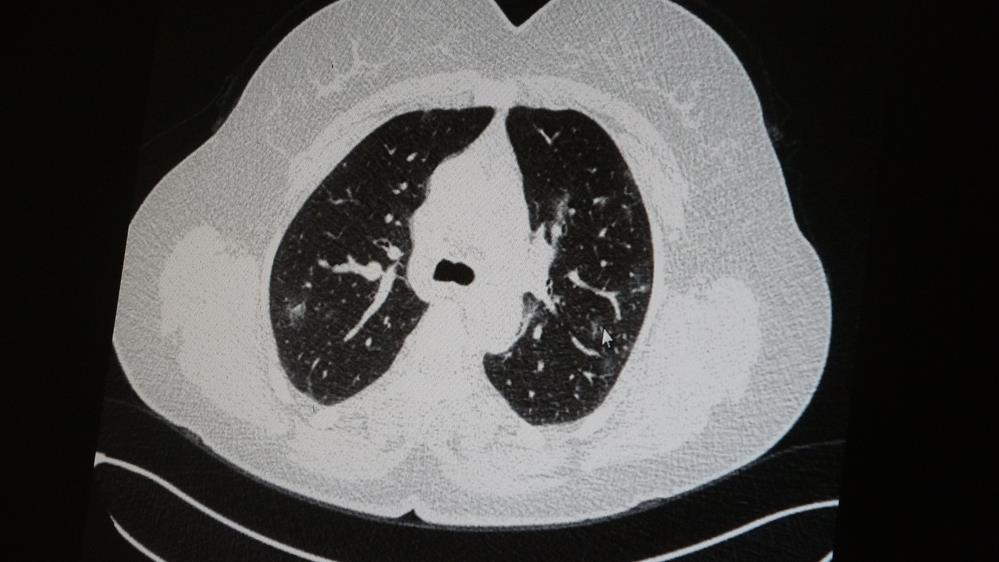

Genç olduğu halde aşı olmayanlarda hastalığın ağır seyrettiğini ifade eden Uzm. Dr. Azar, "Ben gencim, benim bağışıklık sistemim kuvvetli" diyen genç bir hastanın akciğerlerinde ciddi lekelenmelerin olduğunu ve koronavirüs zatürresi olduğunu gördüklerini belitti.

Uzm. Dr. Azar, aynı şekilde aşı olup koronavirüs hastalığına yakalanan bir başka genç hastanın akciğer tomografisinde akciğerde herhangi bir sorunun olmadığını ve hastanın durumunun iyi olduğunu gözlemlediklerini kaydetti. Uzm. Dr. Azar, sürekli şahit oldukları "Keşke biz aşı olsaydık" sözünü bir daha duymamak için herkesi aşı olmaya davet etti.

AŞI OLAN GENCİN TOMOGRAFİSİ AŞI OLMAYAN GENCİN TOMOGRAFİSİ